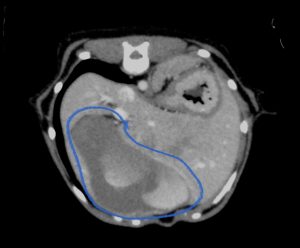

今回治療させていただいたワンちゃんは、数ヶ月前から肝臓(尾状葉乳頭突起)の腫れを指摘されており、CT検査で尾状葉乳頭突起に4センチ大の腫瘤性病変と胃の圧迫、重度の胆嚢拡張を認めました。肝臓腫瘍の初期はほとんど症状がなく(稀に低血糖)、腫瘍が大きくなることで他の臓器を圧迫して症状が出ることが多い印象です。

青線:胆嚢